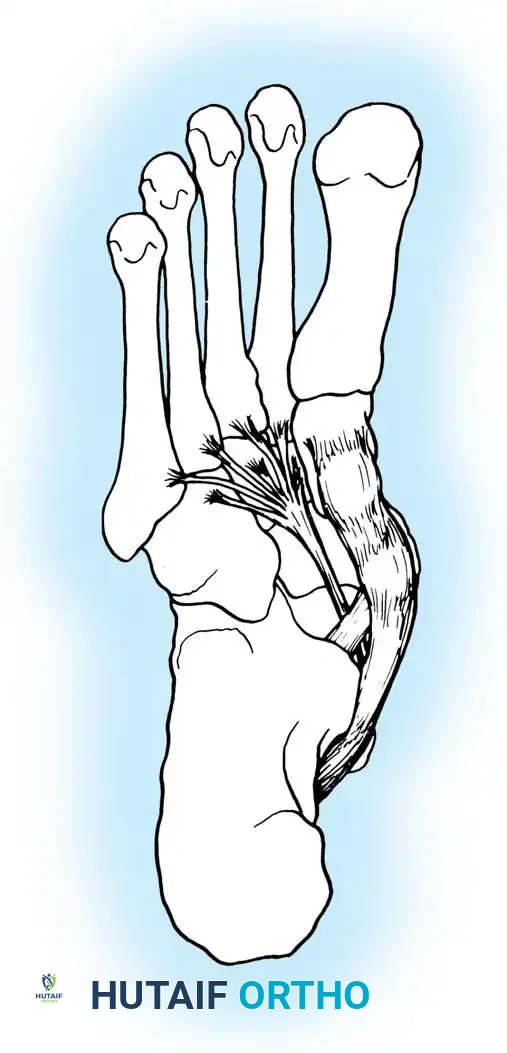

1. Flexor Digitorum Longus (FDL) Transfer:

The FDL is the ideal transfer candidate due to its in-phase firing pattern, proximity, and adequate strength.

* The PTT is excised if severely degenerated, or left in situ if viable.

* The FDL is identified posterior to the PTT, harvested distally at the master knot of Henry, and transected.

* A drill hole is created dorsal-to-plantar through the navicular.

* The FDL is passed through the navicular and sutured to itself or secured with a bio-tenodesis screw under maximal tension with the foot held in plantarflexion and inversion.